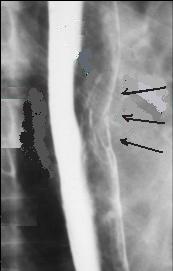

Carcinome

epidermoide : forme stenosant circoferentielle .

Image TOGD mono de contrast |